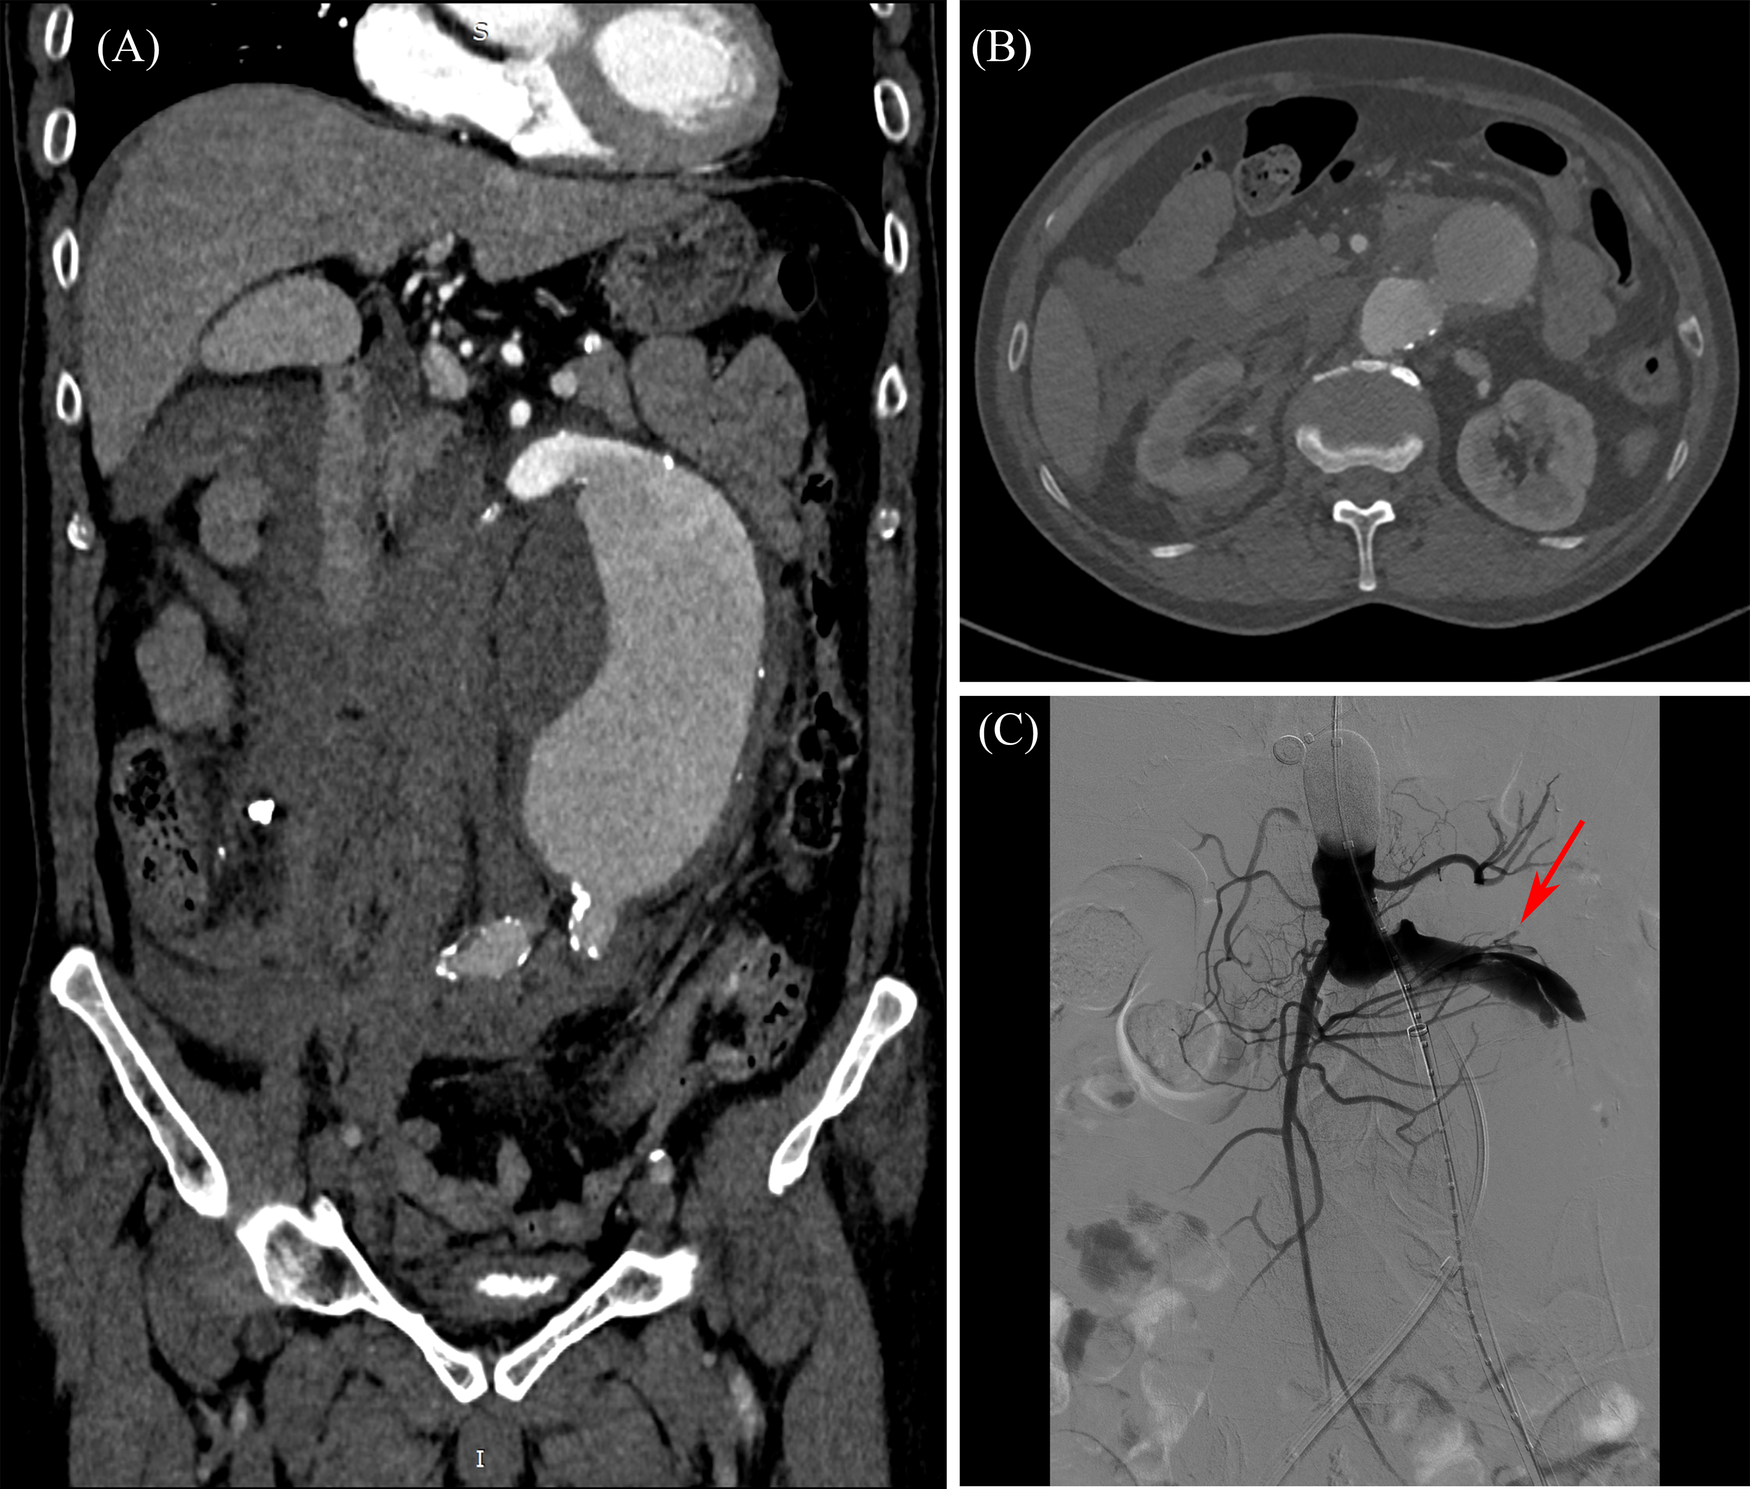

On 26 Jul. 2023, 140 days later, the patient came back to the hospital with severe acute abdominal pain, and was admitted immediately. The patient was scheduled to undergo endovascular aneurysm repair (EVAR) with a covered stent graft following the completion of necessary preoperative evaluations, including abdominal CTA. The blood pressure dropped down to 76/44 mmHg in hospital day 2, and an emergency CT scan was performed. Contrast extravasation with a large retroperitoneal hematoma, as illustrated in Figures 3A,B, was observed comparing to the observation of hospital day 1, and aneurysm rupture was suspected. Emergency interventional procedure followed. A GORE® RLT covered stent graft (31 × 14 × 170 mm) was deployed below the renal arteries. The left limb was extended with a GORE® iliac covered stent graft (16 × 20 × 140 mm), and the right limb was extended with another GORE® iliac covered stent graft (16 × 23 × 140 mm). The digital subtraction angiography (DSA) images (see Supplementary Video S2), recorded during the interventional surgery, are presented in Figure 3C. The rupture site is indicated by red arrow, which locates in the predicted high rupture risk region. The patient was discharged on August 16 following successful treatment and remained clinically stable at the 3-month follow-up visit on November 13, as illustrated in Figure 1C and Supplementary Video S3. At that time, the patient reported no abdominal pain or discomfort and expressed overall satisfaction with the recovery process. No new symptoms or complications were observed.

Figure 3

Preoperative and intraoperative imaging of the abdominal aortic aneurysm. (A) Preoperative CTA–coronal view; (B) preoperative CTA–cross-sectional view at aneurysm neck level; (C) intraoperative DSA–Rupture site captured by DSA imaging.